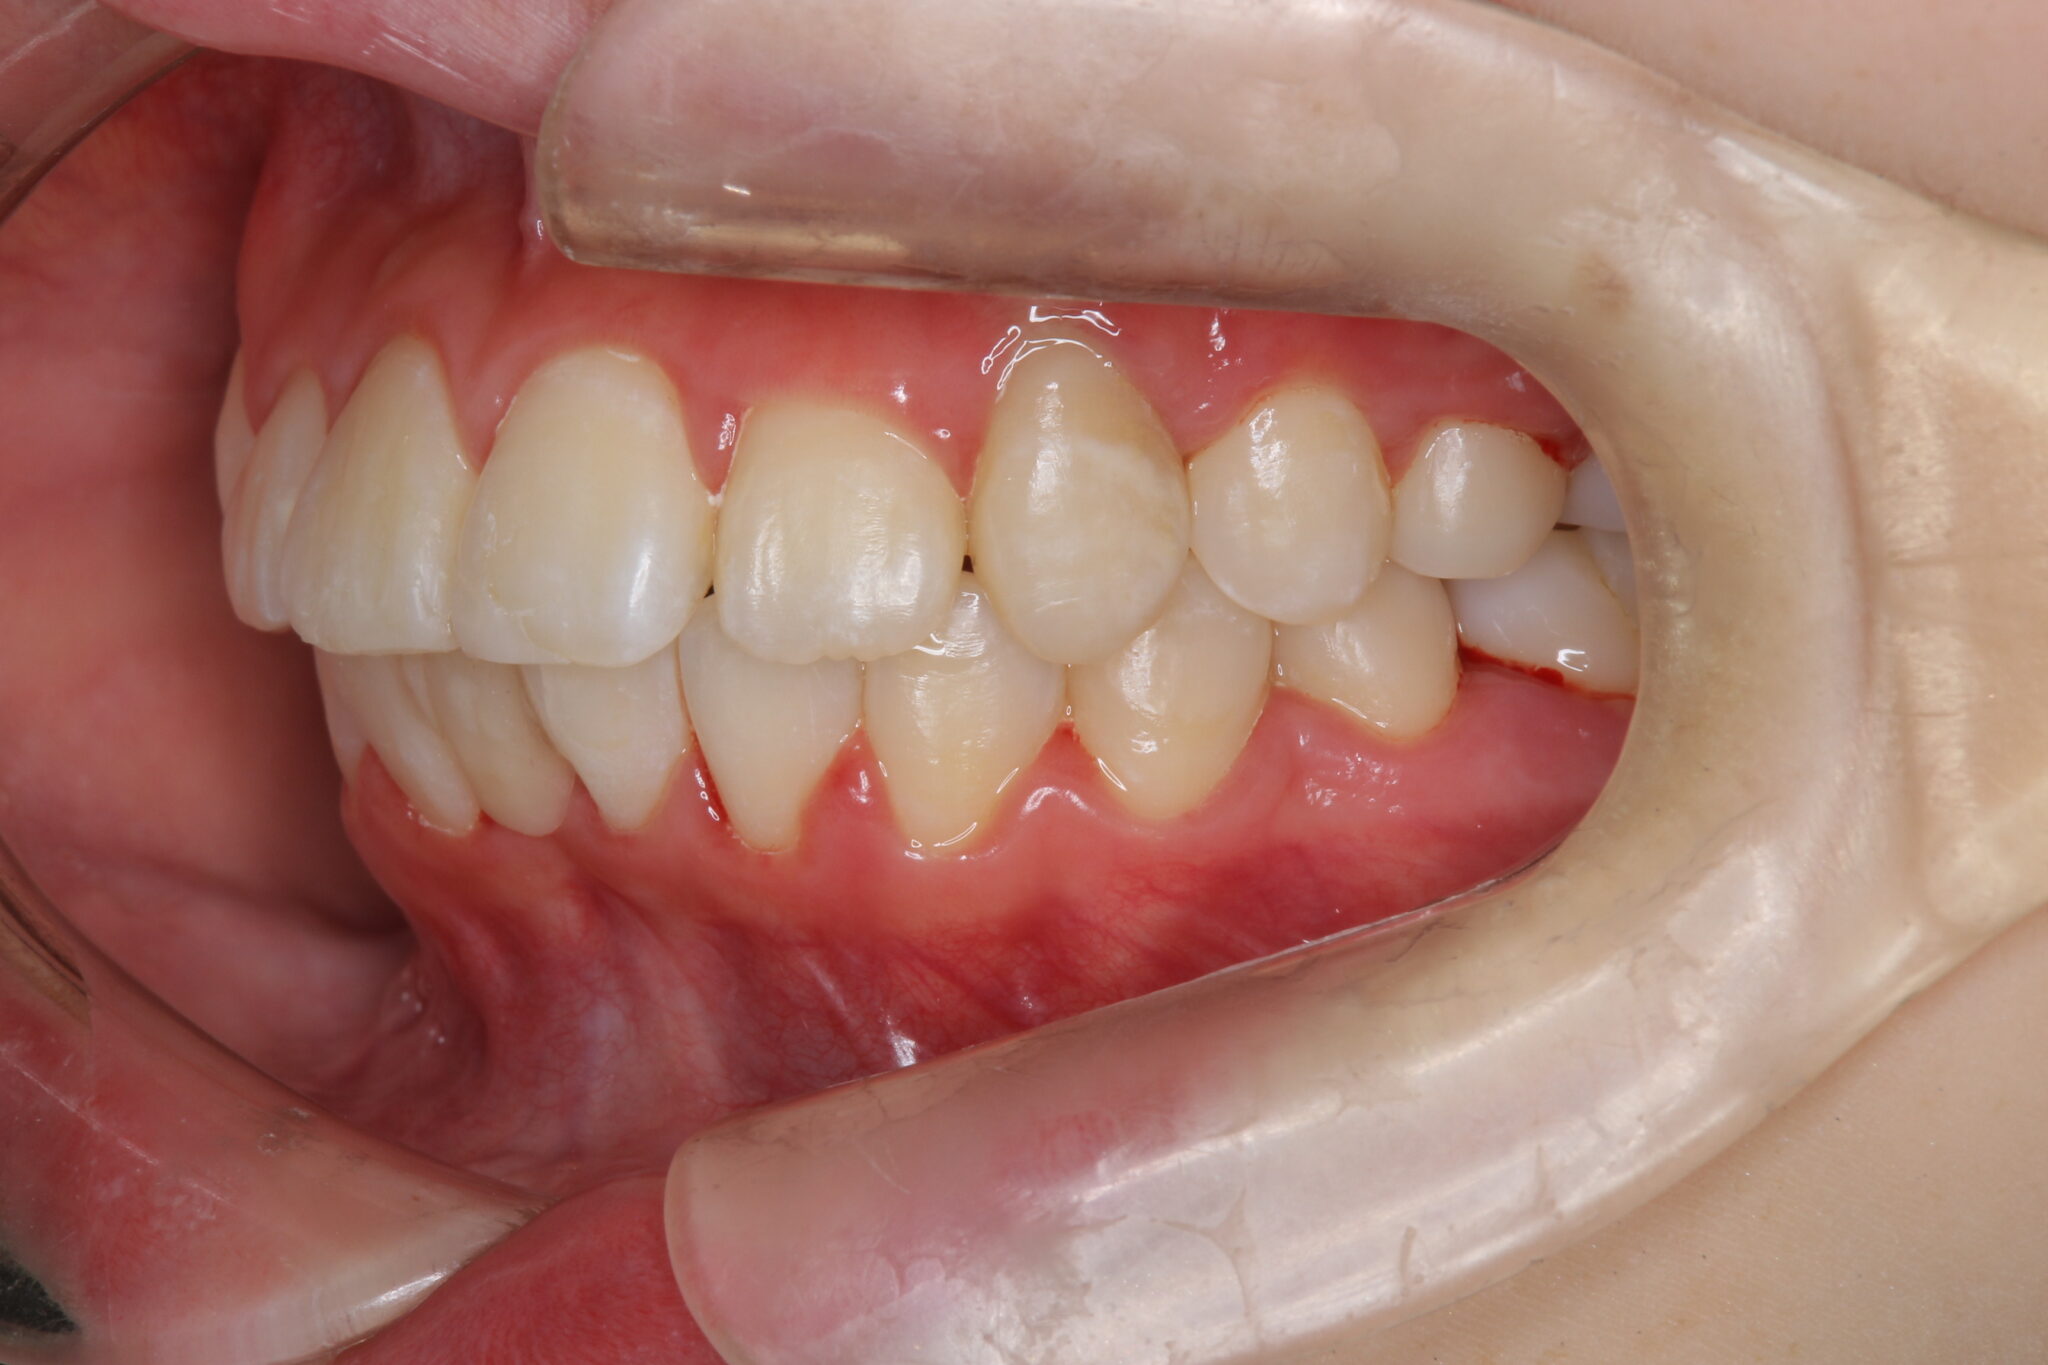

八重歯と出っ歯が気になる

上下顎第三大臼歯(親知らず)

マルチブラケット装置

1年9か月